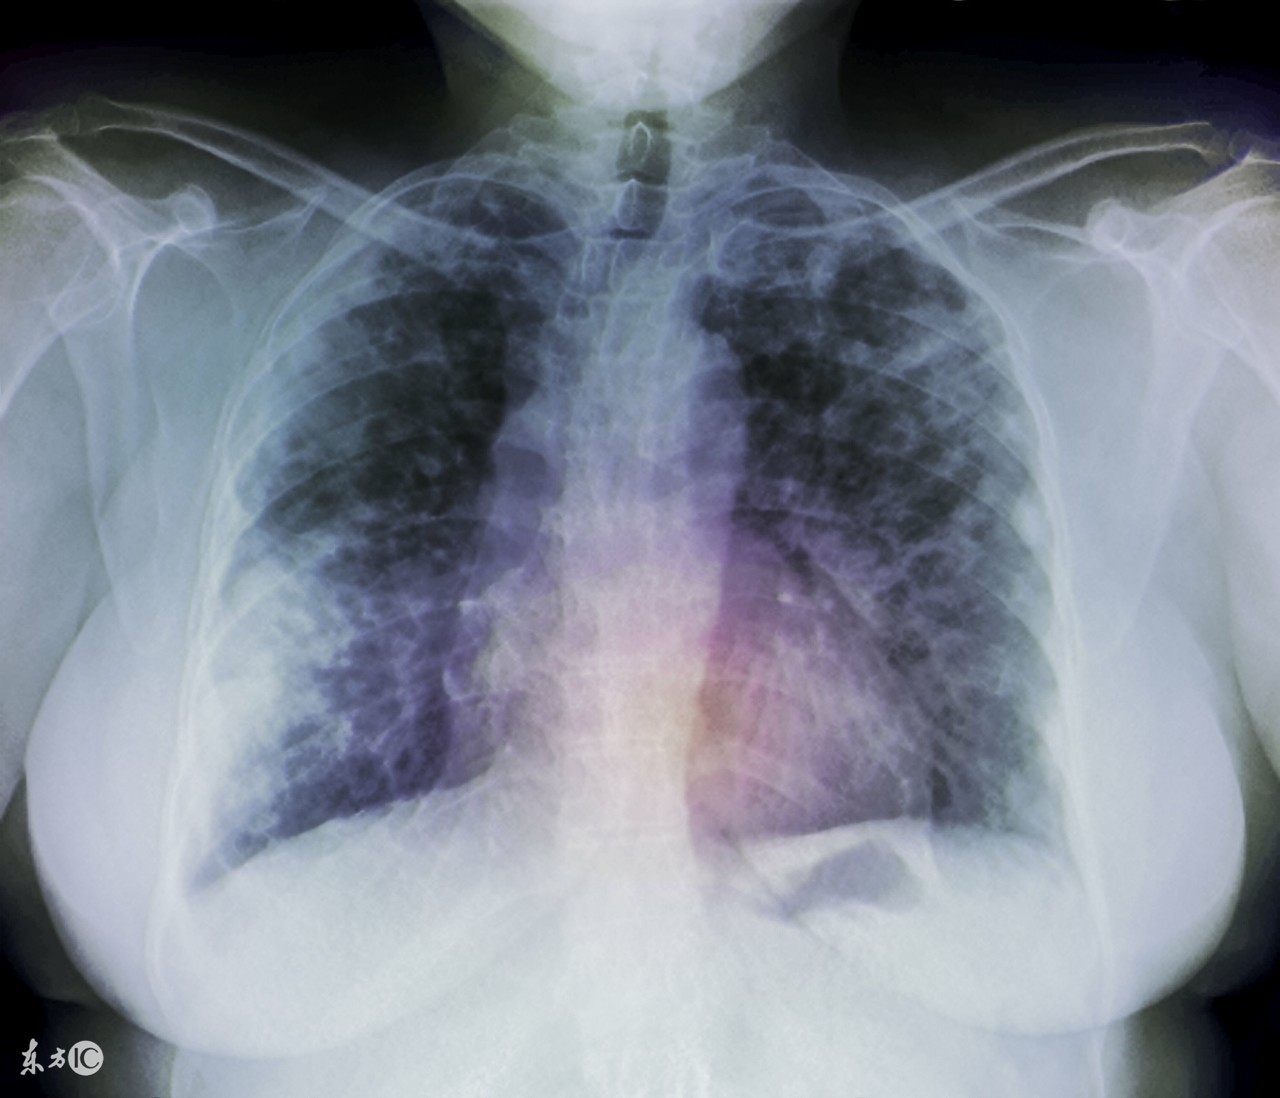

肺腺癌是肺癌的一种,肺腺癌较容易发生于女性及不抽烟者。通常来说肺腺癌的早期一般是没有明显临床症状的,一般在患者在进行胸部X线检查时被发现。肺腺癌的治疗方式有很多,今天针对手术治疗这种治疗方式来给大家具体做个介绍。